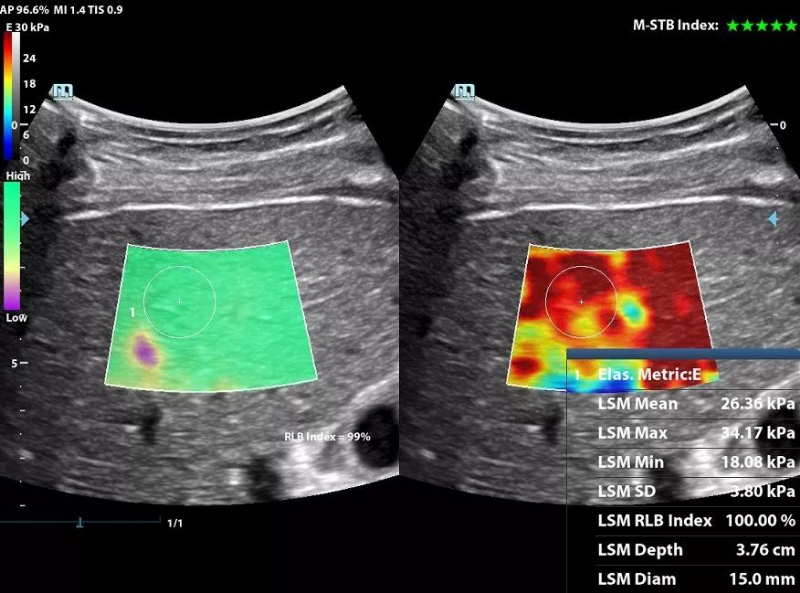

To meet such requirements, the DC-80 with X-Insight delivers the leading Sound Touch Elastography (STE) technology with real time 2D shear wave imaging and modulus quantification for easy tissue stiffness assessment in wide applications including liver, breast, thyroid and MSK. With the help of reliability map and motion stability index, STE provides quantifications with more accuracy and reproducibility for better diagnosis.

STE of liver cirrhosis

STE of thyroid nodule